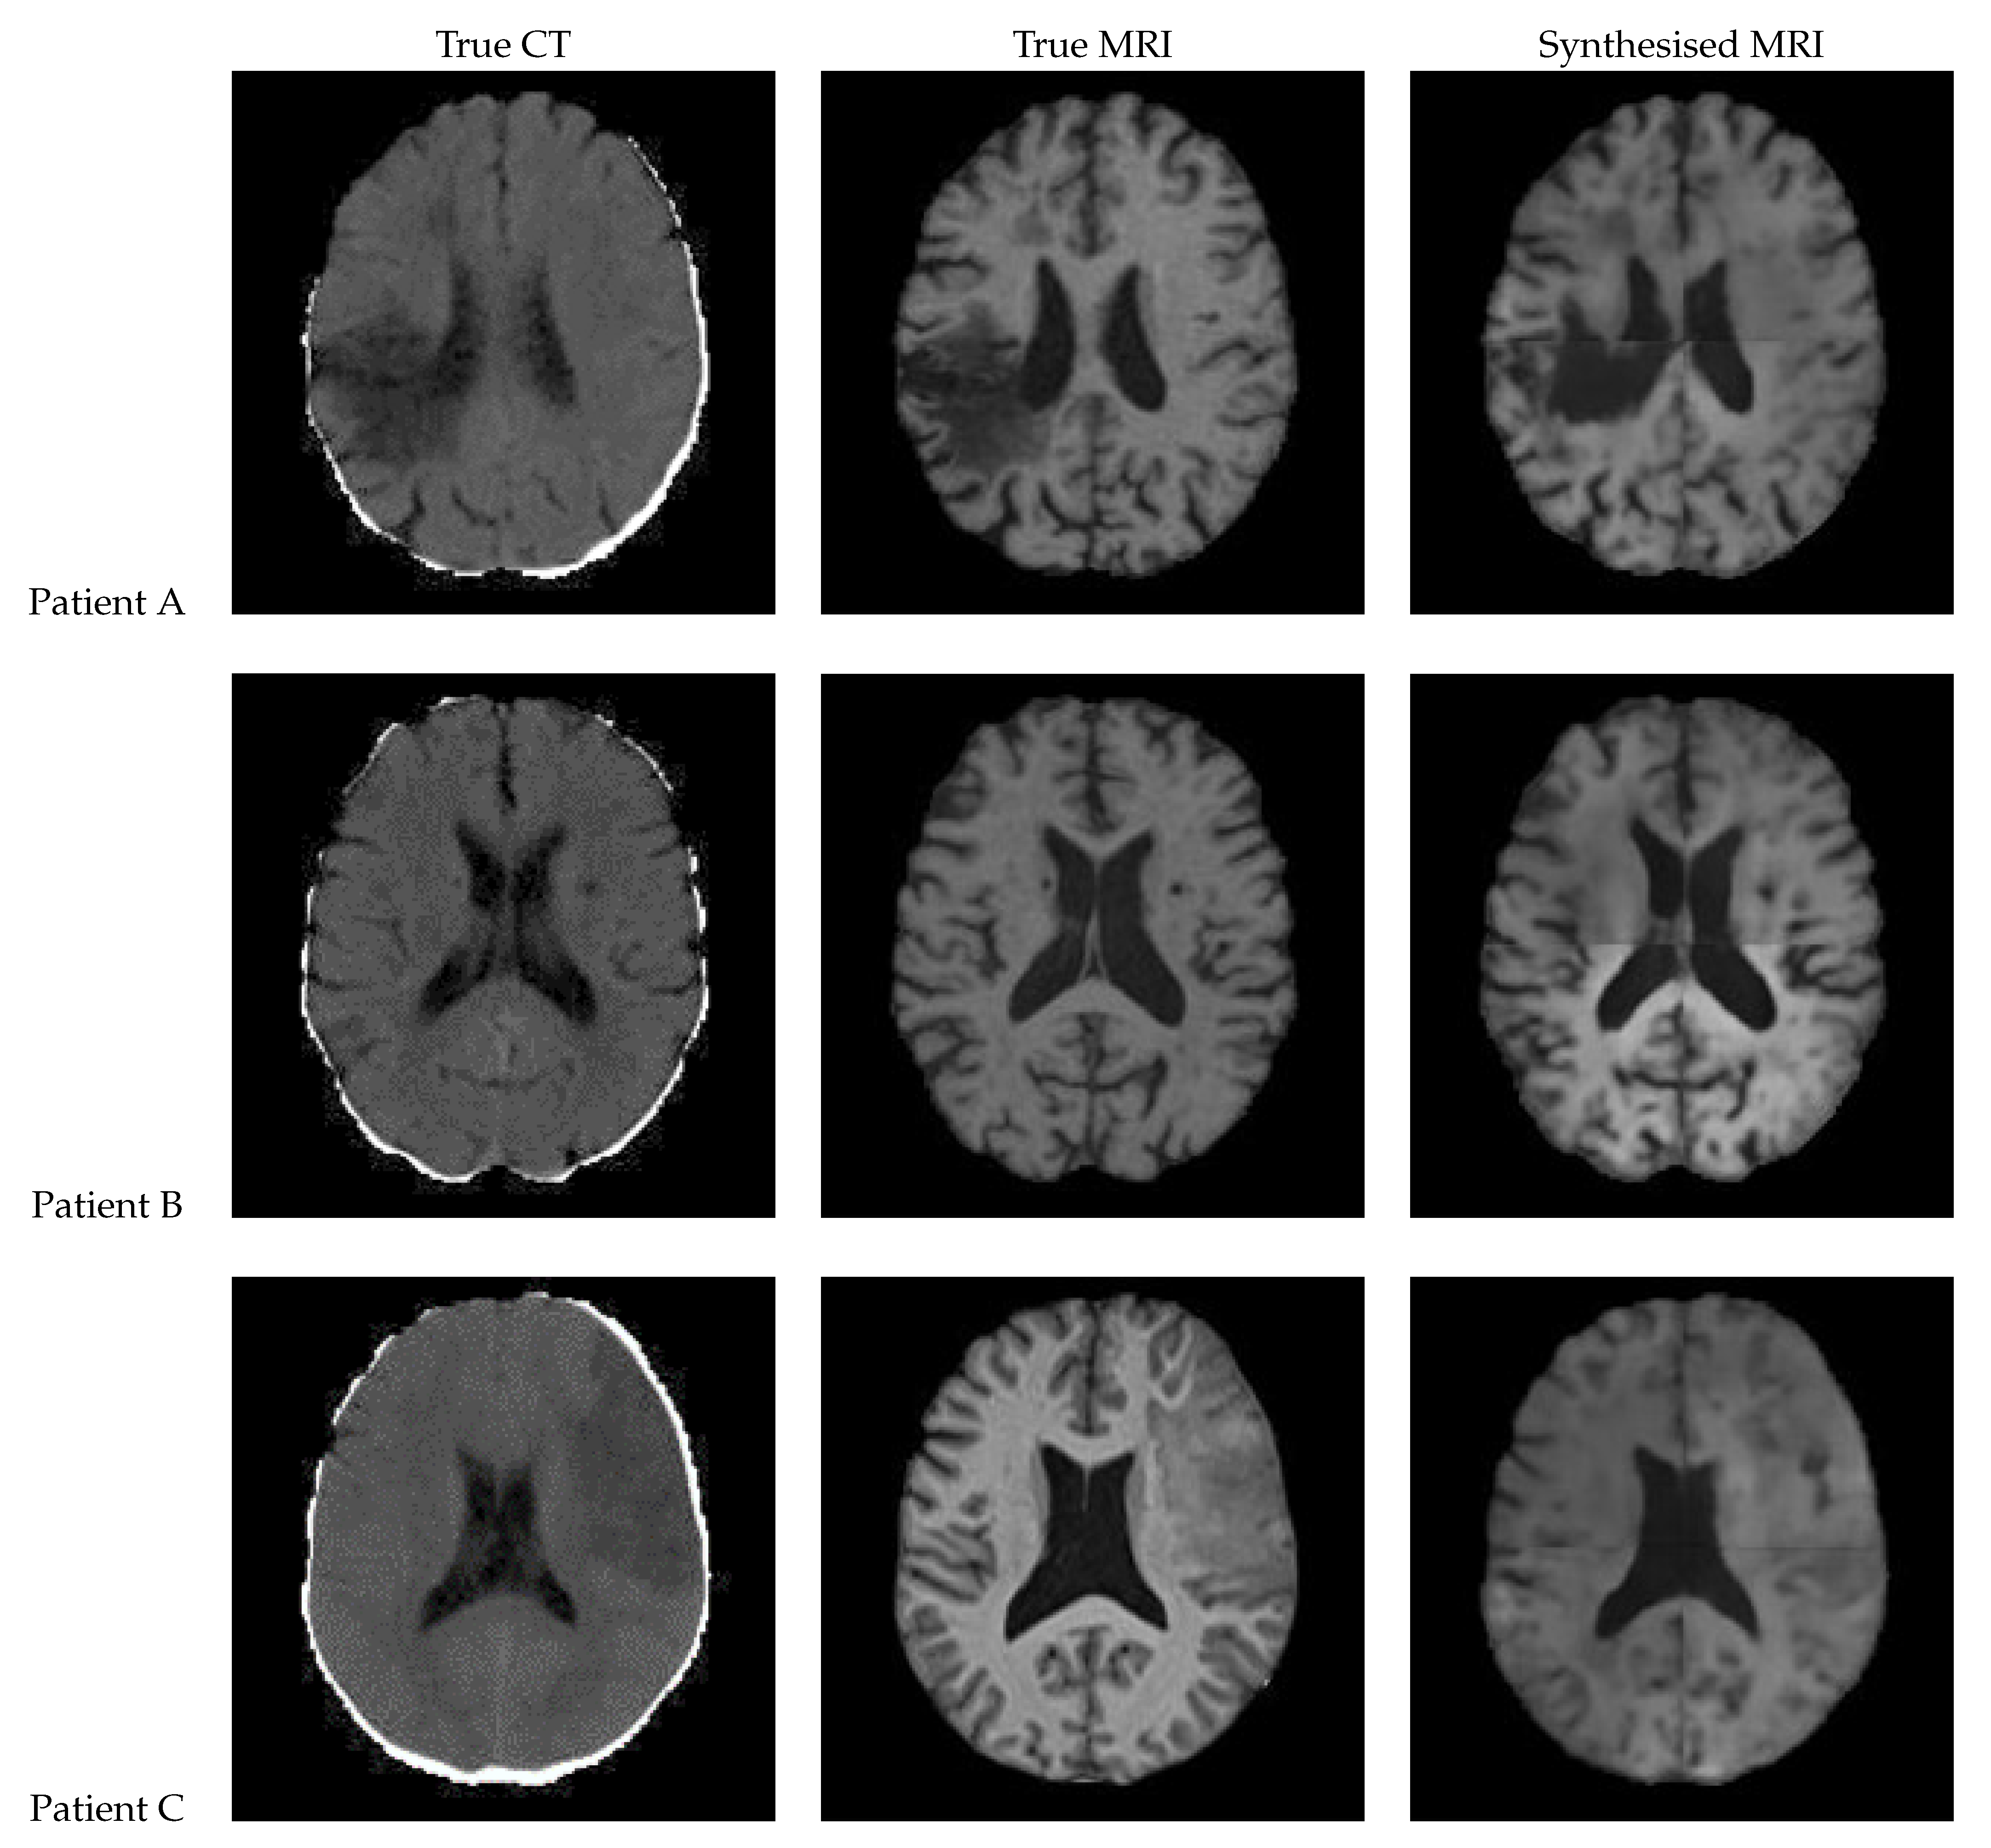

Figure 13 shows a slice of the synthetic MRI generated by a 3D UNet using an UpSampling layer and a Convolution layer instead of the Conv3DTranspose layer. The lesion for Patient A is clearly visible and appears similar in shape to the true MRI. The lesion in the Patient C is also discernible, albeit faint and lacking a clear outline. All three synthetic images show good contrast and likeness to the original image.

Figure 13. Axial slices of CT Scans (Left), True MRIs (Center), and Synthetic MRIs generated by UNet V2 (Right).